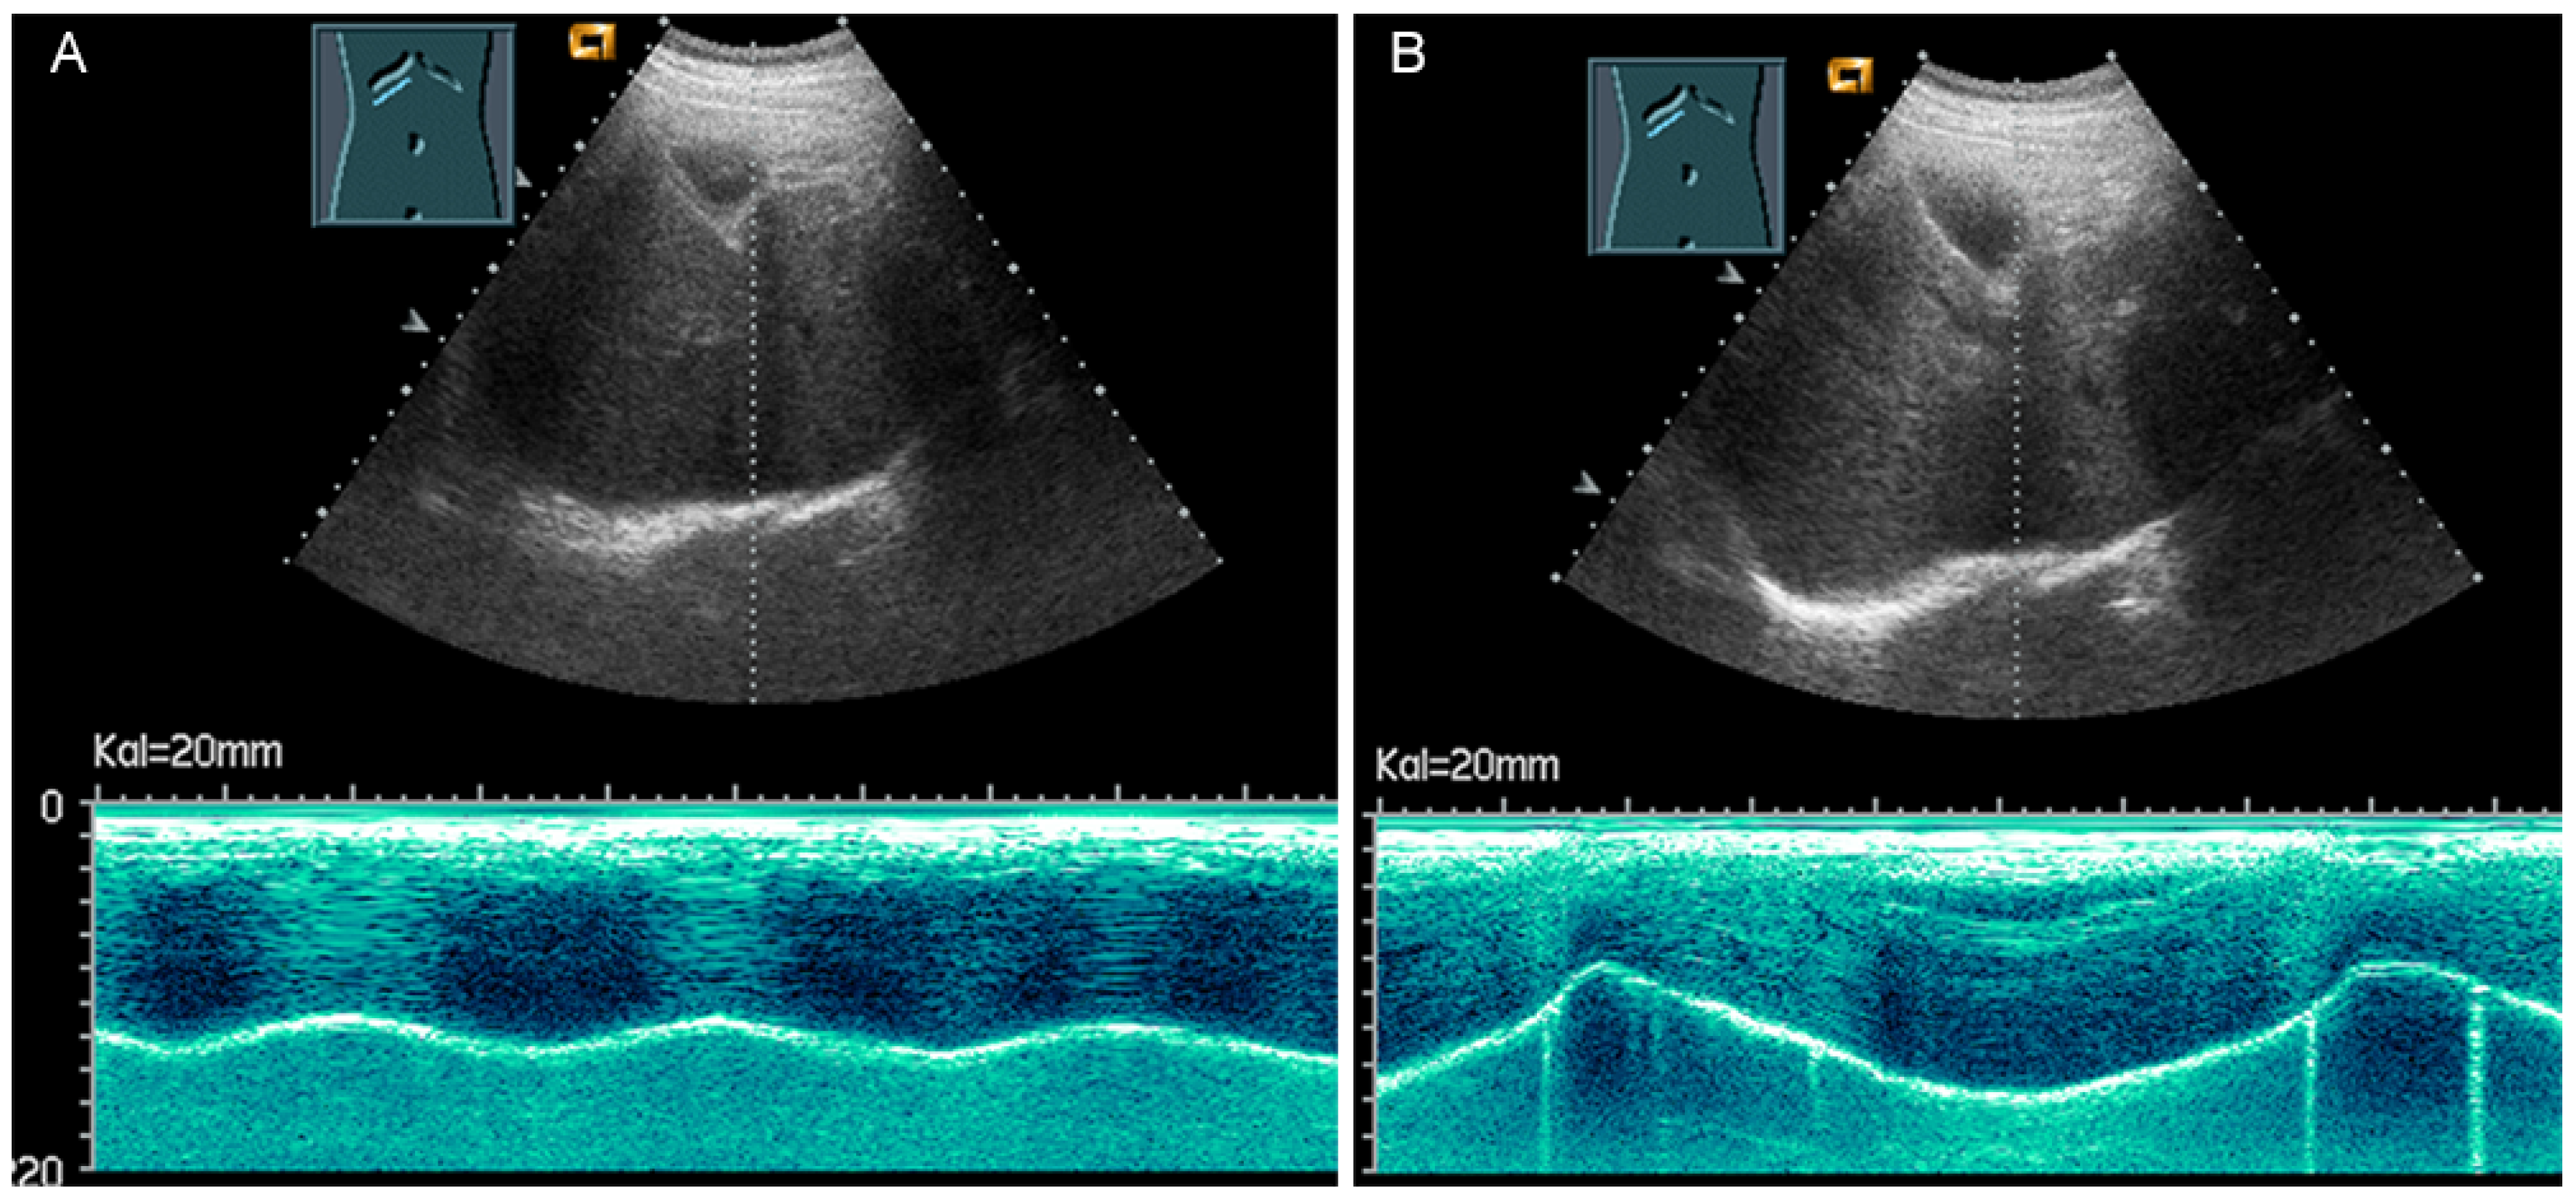

3.3.2. Diaphragm Excursion

Diaphragmatic excursion is measured in M-mode US with a low-frequency probe (2.5–5.0 MHz) in an anterior subcostal view through the liver window. The transducer should be positioned between the middle clavicular line and the anterior axillary line and directed medially, cranially, and dorsally to visualize the posterior third of the right diaphragm, approximately 5 cm lateral to the inferior vena cava foramen [52,53]. The amplitude (distance between the highest and the lowest points of the diaphragmatic movement) and the speed are measured in both quiet breathing and forced inspiration (the sniff maneuver) (Figure 32) [52,53]. The amplitude of diaphragmatic excursion is highly dependent on physical constitution and ranges from approximately 1–2 cm (resting breathing) to 7–9 cm (forced breathing) [59]. The diaphragm excursion can be determined only in spontaneously breathing patients.

Figure 32.

Illustration of diaphragmatic motility during quiet (A) and deep breathing (B) in a subcostal view.